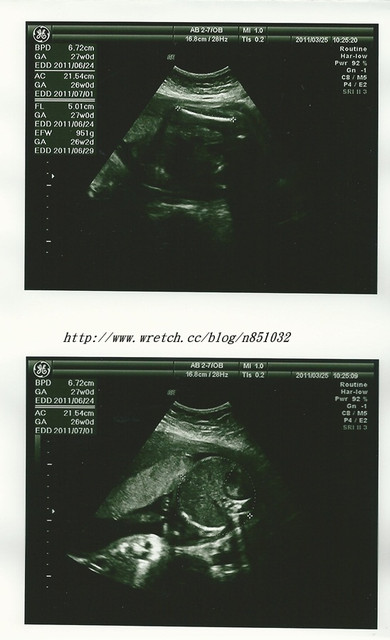

二寶

sophie

頭圍BPD:7.42

cm (6.72cm) 頭圍BPD:

7.81cm 肚圍AC:

25.38 cm(21.54CM) 肚圍AC:23.91

CM大腿骨FL:5.26

cm(5.01CM) 大腿骨FL:5.56

CM體重EFW:1347

g(951g ) 體重EFW:1333

g

頭圍BPD:6.72

cm (5.62cm) 頭圍BPD:

6.79cm 肚圍AC:

21.54 cm(16.70CM) 肚圍AC:

20.52CM大腿骨FL:5.01

cm(3.9CM) 大腿骨FL:

4.97CM體重EFW: 951

g(487g ) 體重EFW:

886g